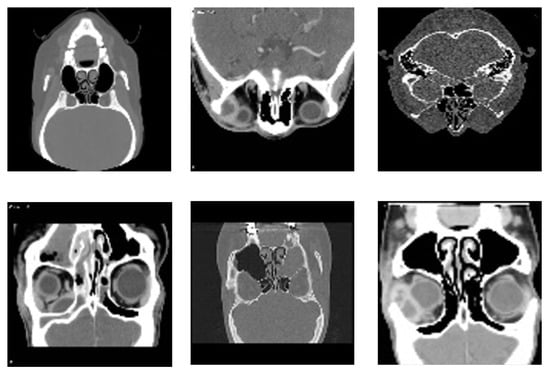

The Radiopaedia website [39] provides a diverse collection of cases featuring extensive imaging studies, including CT scans and MRIs from multiple individuals, each representing a unique subject. All images have been carefully annotated by radiologists, making this repository a valuable resource for both research and educational purposes. These datasets offer critical insights into diagnosis and classification. However, as highlighted in [40], publicly available datasets on sinus diseases remain scarce. To address this gap, we undertook a rigorous effort to filter and refine a dataset specifically focused on sinus pathologies. Our approach involved systematically reviewing the extensive Radiopaedia repository [39], which contains images related to various medical conditions. We carefully identified, categorized, and extracted only the most relevant and high-quality sinus-related images. This meticulous curation ensured that our dataset is both comprehensive and specifically tailored to sinus pathologies, enhancing its utility for research in AI-assisted diagnosis. Furthermore, to facilitate further advancements in the field, we have made this dataset publicly available for all research purposes in [41]. Figure 3 illustrates samples from the dataset.

Figure 3.

Representative samples from the dataset, showcasing diverse imaging types and anatomical views of sinonasal regions used for training and validation of the proposed detection model.

The data collected from the website [39] are distributed across two classes: healthy, consisting of 37 instances, and unhealthy, consisting of 100 instances, for a total of 137 samples. Imaging data were collected from 137 participants, with scans obtained from multiple clinics to ensure diversity in the analysis.